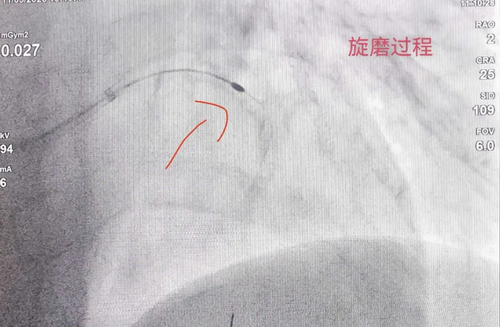

面对这一难题,心血管病科团队果断决定,实施冠状动脉旋磨术。什么是冠状动脉旋磨术? 简单来说,就是用一枚镶嵌着微小钻石颗粒的旋磨头,以每分钟高达15万转的速度高速旋转,像"金刚钻"一样将血管壁上的严重钙化斑块打磨成微粒。这些微粒非常微小,可以随血液循环安全排出,随血液循环安全排出,血管恢复弹性,为球囊扩张和支架植入创造条件。

术中,团队先后3次使用1.5万转/分的旋磨头,精准击碎钙化"硬壳"。旋磨成功后,顺利行球囊扩张并于前降支植入支架。同期,团队还对右冠病变进行了介入处理。术后患者血管开通效果理想,目前正在康复中。